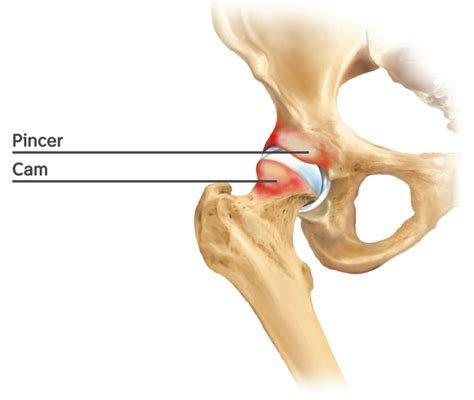

It is important to distinguish between the types of hip impingement. While Cam Impingement specifically relates to the femoral head, other types can occur either alone or in combination. The following table provides a breakdown of the differences:

Type Anatomical Issue Impact

Cam Impingement Bony bump on the femur head Causes friction against the socket rim

Pincer Impingement Excessive coverage by the socket Pinches the labrum between bone edges

Combined Impingement Mix of both Cam and Pincer Most common clinical presentation